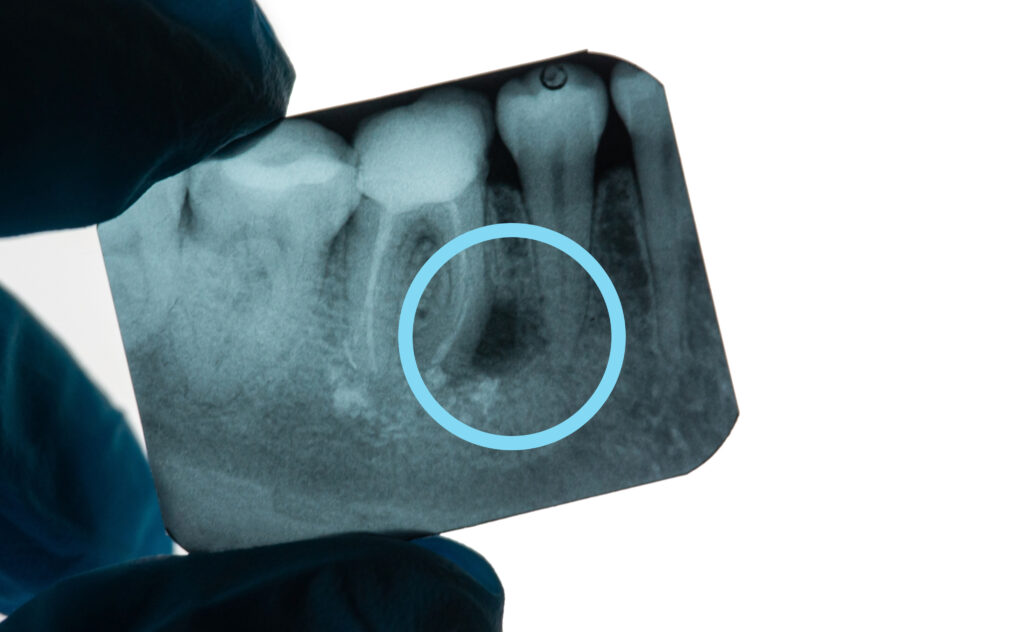

Un granuloma dentale è un’infiammazione cronica che si forma alla base della radice di un dente, solitamente come conseguenza di una carie non trattata, un trauma o un’infezione batterica penetrata fino alla polpa dentale. Si manifesta spesso senza sintomi evidenti, ma nei casi più gravi può provocare dolore, gonfiore o la formazione di un ascesso. Può essere individuato da una semplice radiografia, e si presenta come una macchia scura, più o meno circolare, collocata sopra la radice del dente.

Granuloma Dentale periapicale adiacente alla radice dentale